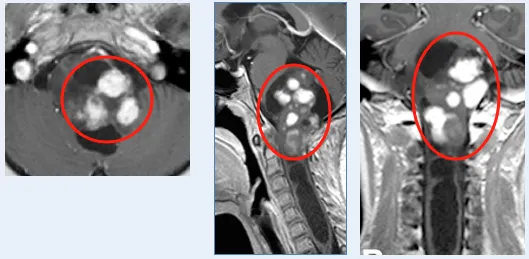

首次找到巴教授时,术前轴位(a、b)及矢状位(c)MRI显示肿瘤已极度增大,自中脑向双侧丘脑、脑桥及小脑广泛浸润。鉴于既往治疗未能有效控制肿瘤,实施手术。巴教授术中完整切除外生型毛细胞型星形细胞瘤,术后轴位(e、f)及矢状位(g)T1加权增强MRI证实肿瘤全切。

术后患者未出现新的神经功能障碍,恢复顺利。术后10年随访(h),患者状况良好,未见肿瘤复发。